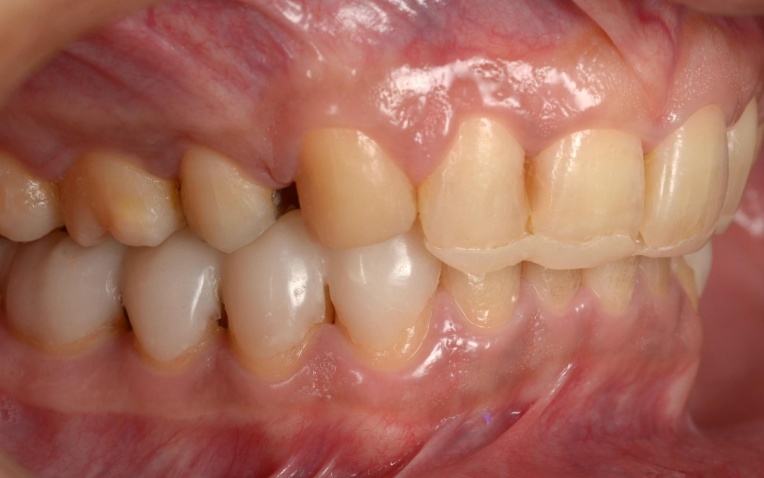

治療中

まずはバイト挙上を行います。上顎には、下顎の位置を安定させるための「スプリント」を使用し、下顎奥歯には噛み合わせを調整するための仮歯を装着しました。

この状態で下顎にのみワイヤーを装着し、安定した下顎の位置をキープしながらワイヤー矯正治療へ移行します。

矯正治療は、顎の痛みや噛み合わせの違和感などが落ち着き、安定した状態で進めることが重要です。

そのため、上顎前歯には上顎のスプリントを必要な部分だけカットして歯に直接接着し、噛み合わせの高さを維持するストッパーとして活用しました。

これにより、上顎の装置が矯正のガイド役となり、安定した下顎の位置を崩さずに精密なワイヤー矯正を行うことが可能です。

また、上顎には上下の噛み合わせの前後関係を整えるための補助装置「顎間ゴム」を使用し、噛み合わせを正しい位置関係へ導く「咬合(こうごう)誘導」を行っています。